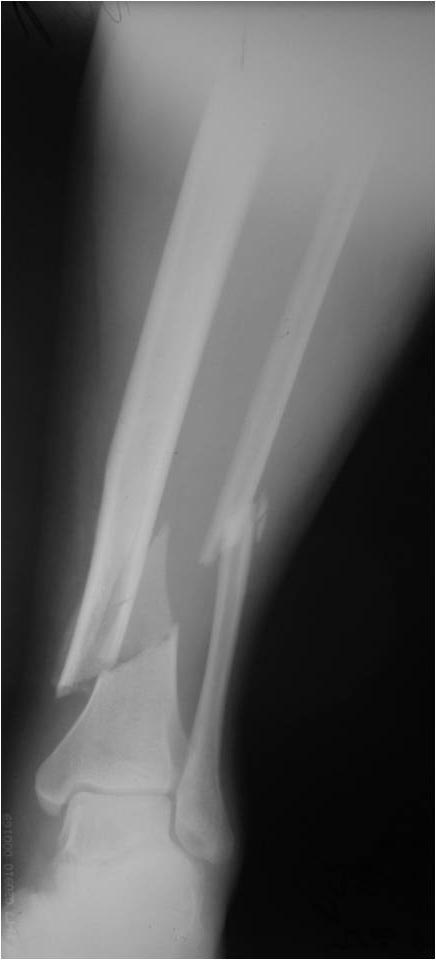

[Ortho] Деформация фиксатора после падения

первичные снимки и остальные качеством получше.

Имя     : AP2.jpg

Тип     : image/jpg

Размер  : 28998 байтов

Url     : http://weborto.net:8080/pipermail/ortho/attachments/20121105/5ddbb42f/attachment-0008.jpg